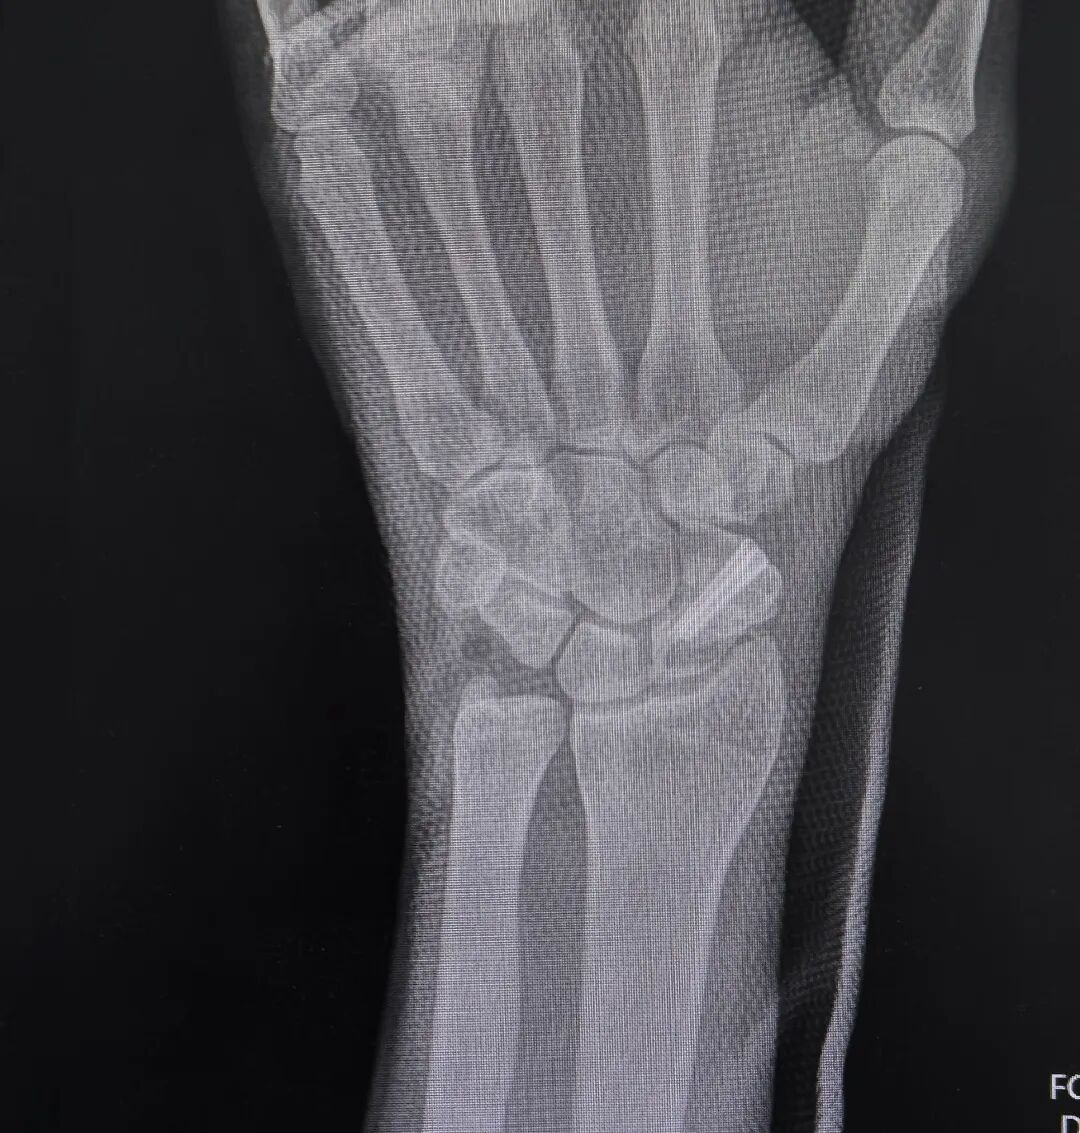

郭阳院长仔细翻阅他 20 多年来的病历,结合最新的检查结果,指着影像片上的病灶,耐心解释:“你这是典型的陈旧性舟骨骨不连,骨折端已经硬化、萎缩,周围腕关节也出现了代偿性磨损,普通手术很难彻底清理硬化骨、稳定固定,容易再次不连,需要植骨重建 + 内固定技术,才能从根源上解决疼痛,恢复腕关节功能。”

术后复查的 X 线片上,曾经断裂、硬化的舟骨被稳稳复位,植骨块位置良好。